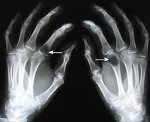

Посттравматический артроз

Посттравматический артроз – это хроническое прогрессирующее поражение сустава, возникшее после его травматического повреждения. Чаще развивается после внутрисуставных переломов, однако может возникать и после травм мягкотканных элементов (связок, менисков...